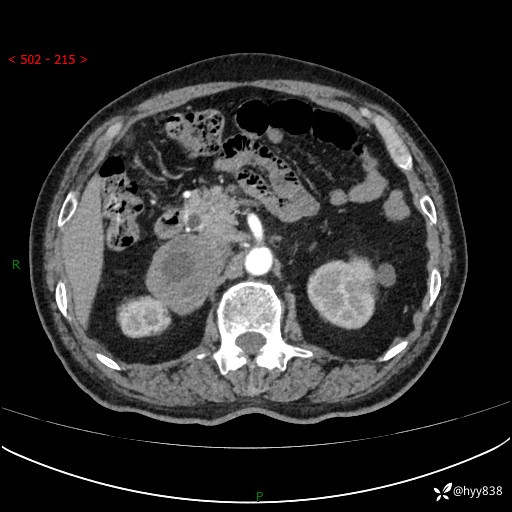

【患者信息】:76岁/男

【主诉】:检查发现右侧肾上腺占位6天

【现病史及既往史】:患者6天前体检发现右侧肾上腺占位,无腰痛,无放射痛,无尿频、尿急、尿痛及肉眼血尿,无畏寒、发热,无恶心、呕吐,今为求进一步治疗,遂来我院就诊,门诊拟“右侧肾上腺占位”收住入院。 起病以来,患者精神、饮食、睡眠可,大小便如常,体力体重无明显变化。

【检查】:肾上腺CT平扫+增强